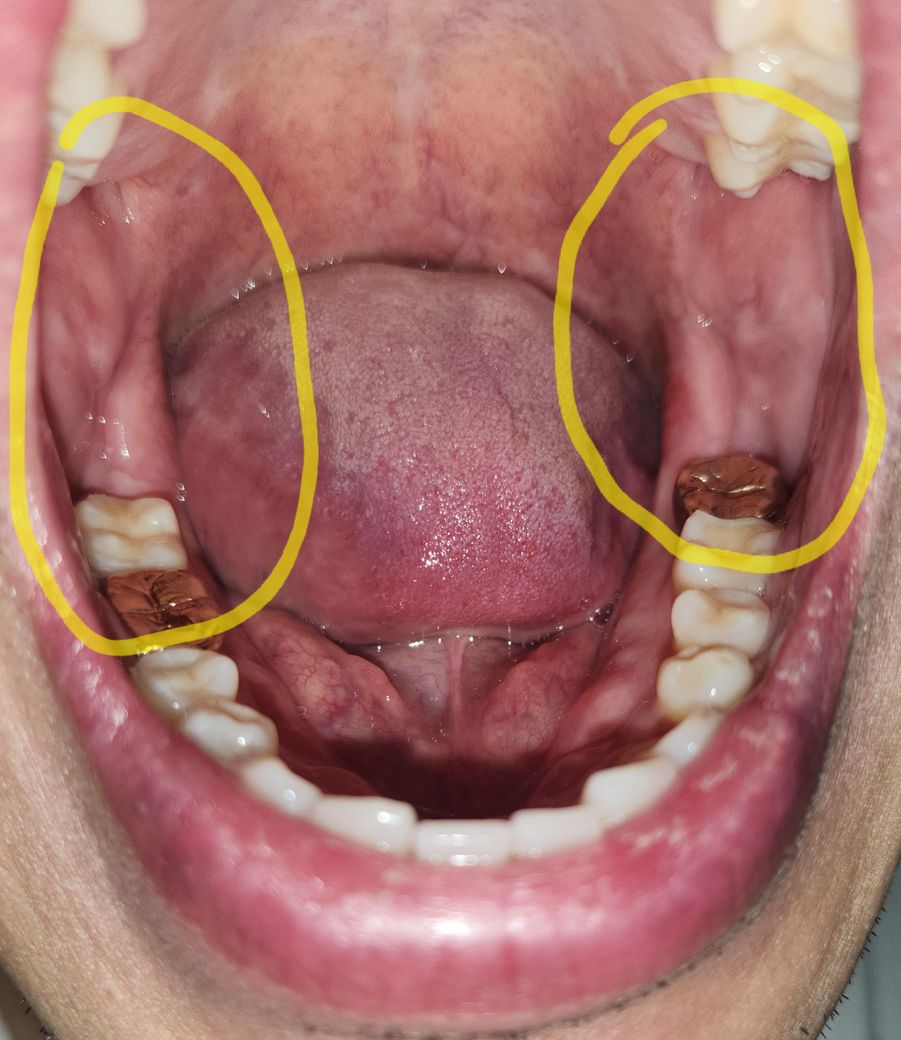

볼 안쪽 살 볼록해서 접힘 (기존 이갈이 협점막 백선 있음)

기존에 수면 이갈이가 심해서 협점막 백선 생김

양 볼 안쪽 살이 많이 볼록해서 접히는데

원래 이렇게까지는 아니었어요

1.접히는 부분 들춰보면 새빨간데 문제없나요?

2.볼 안쪽살이 볼록해서 접히는 이유가

이갈이에 의한 데미지, 붓기 인가요?

3.살찌면 뱃살나오듯이 단순 볼살 인가요?

• 1번 째 사진